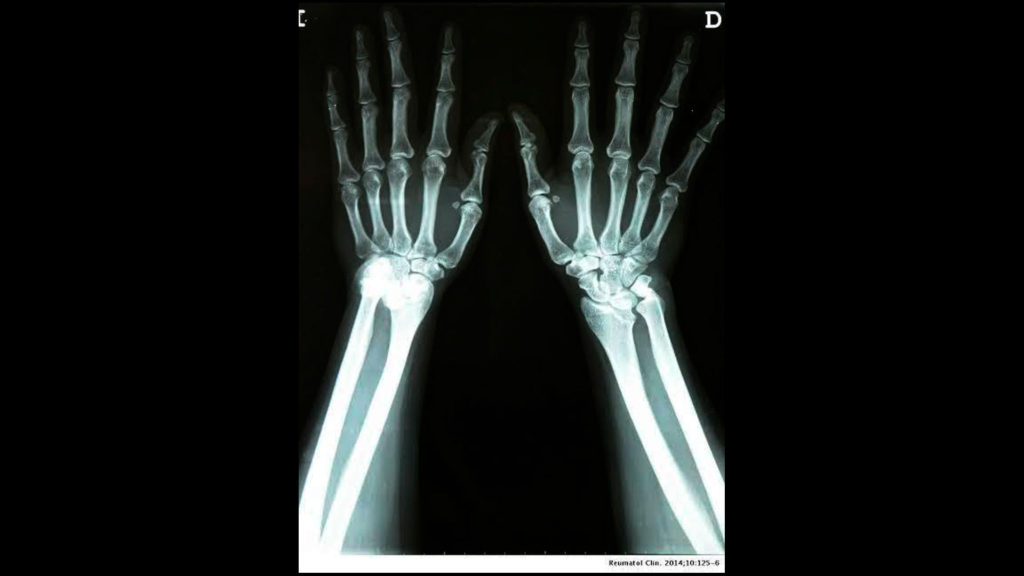

Radiografías comparativas

Es la radiografía tomada de ambos lados derecho e izquierdo de un segmento específico para determinar pequeños cambios imperceptibles al ojo humano mediante la comparación de ambos lados.